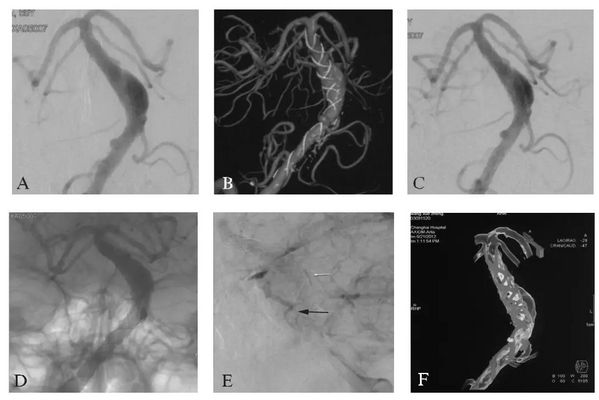

MRI:头颅MRI平扫显示椎基底动脉均增粗,基底动脉偏向左侧并超过鞍背外侧,基底动脉桥脑水平从左侧压迫脑干,脑干无明显水肿。T₂WI可见增粗的基底动脉内有血栓形成(图16-1A)。

CTA:椎基底动脉明显增粗,以右侧椎动脉为优势椎动脉,双侧椎动脉硬化,椎基底动脉汇合处明显向左侧偏移,基底动脉中下段可见梭形动脉扩张(图16-1B)。

DSA:前后位的右侧椎动脉造影显示右侧椎动脉及基底动脉增粗,基底动脉中下段管腔膨大,椎基底动脉明显向左侧偏移(图16-1C)。

A:MRI平扫T₂WI轴位示基底动脉血管腔内血栓形成;

B:CTA三维成像(后前位观);

C:椎基底动脉冗长扩张症血管造影图像